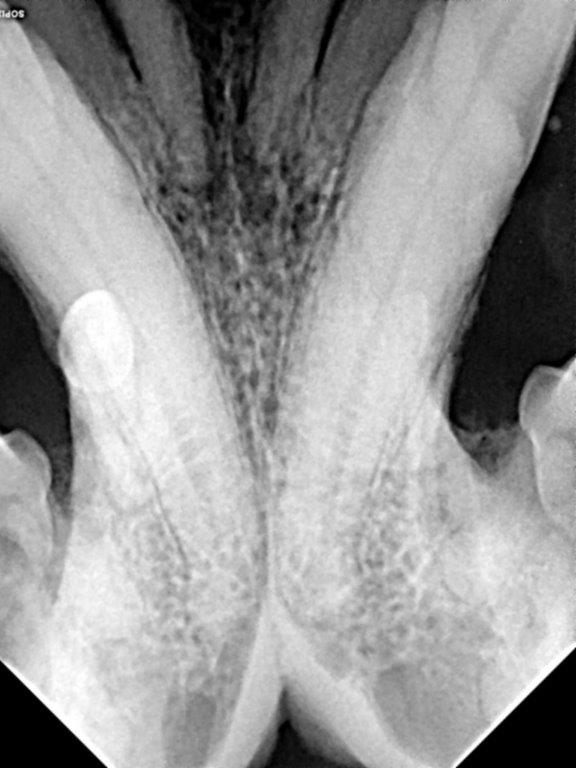

When under GA and the teeth were probed there were 10mm probing depths lingually on both lower canine teeth with severe inflammation of the gingiva bucally and extending below the tongue (see photo). The gingiva around 104 was hyperplastic and inflamed and so friable it just disintegrated when I swabbed it. The other teeth also had increased probing depths. On the xray resorption and ankylosis of many of the teeth can be seen. There was a large lesion in the buccal mucosa possibly where 404 contacted the lip.

A large gingival flap was made and 203, 202, 201, 101, 102, 103, 104, 105 and 106 were extracted using a vet tome, elevators and luxators. The friable gingiva was resected just above the mucogingival margin. The buccal mucosa was bluntly dissected the sutured to the palatal mucosa. 304, 404 and 405 were extracted using the vet tome. The owner was warned pre-operation of the complication of jaw fractured. This did not occur as I used the vet tome, burred away some alveolar bone, used gentle elevation and was patient!. The gingiva between the canines, where the lower incisors had been previously extracted, was also friable. I placed cruciate sutures over the canine sockets to hold the blood clot in place but could not suture the gingiva closed as the tissue was too friable and inflamed. The area between the lower canines was left to heal by secondary intention.